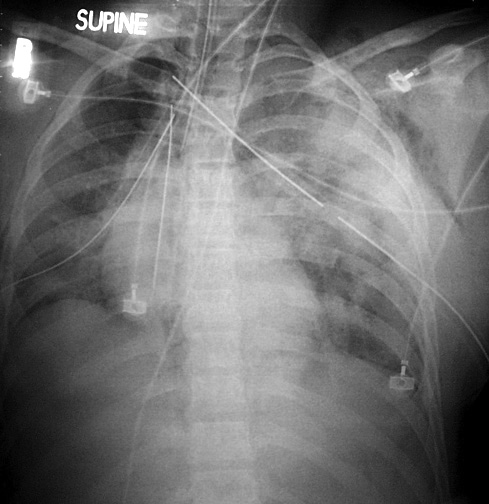

Here is the patient’s Echocardiogram and CXR:

CXR shows a widened mediastinum and the echo shows a proximal dissection flap

The following CXR demonstrates severe left chest trauma – Aortic Injury should be a concern in these circumstances:

An entirely normal chest x-ray is somewhat reassuring in the first instance but unfortunately many CXRs in the Emergency Department are either inadequate or have non-specific abnormalities. So while CXR is a very useful test in chest trauma it may miss up to 11% of patients with Aortic Injury if used alone as a single test to exclude this injury. When you look retrospectively at patients with a proven Aortic Injury up to 50% have no specific findings on their CXR.